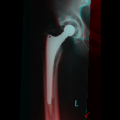

b. Medical application: Hip prosthesis registration

Hip replacement is a surgical procedure in which the hip joint is replaced by a prosthetic implant. Such joint replacement surgery generally is conducted to relieve arthritis pain or fix severe physical joint damage. In the short term post-operatively, infection is a major concern. Deep infection will often require one or two stage revision surgery. Recurrent dislocation is another indication for revision. In the long term, many problems relate to osteolysis from wear debris. An inflammatory process causes bone resorption and subsequent loosening or fracture often requiring revision surgery.

The following figure shows a result of our method. The red channel of the first image represents the template. By applying the inverse of the recovered transformation to the observation, we get a registered image shown in the green channel. The contour overlay image shows the contour of the registered observation object in yellow color over the template image.

Registration of hip prosthesis X-ray images. Each image pair has been taken over a period of time about the same patient. The overlayed contour in the second row shows the aligned contour of the corresponding image in the first row. For each pair, we have also evaluated the measure.